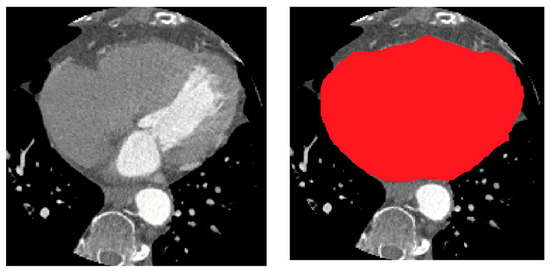

To address the imbalanced class distribution of vessel areas, various strategies can be implemented to enhance the trained network’s performance. The training process incorporates a combined binary cross-entropy (BCE) and soft dice loss (DSC) with equal weights as the loss function to evaluate the agreement between ground-truth patches and regions identified as vessels by the network within the heart ROI. The network was specifically trained within the heart ROI to differentiate features that distinguish vessels from the surrounding heart tissue. Training patches were obtained by isolating the heart region from the CTA slices, as illustrated in Figure 5, ensuring that each training patch had a corresponding mask; patches without annotation masks were excluded from the training dataset.

The high DSC score of 0.98 suggests that the ResUNet model was able to accurately identify and delineate the heart region within the CTA images. This is a significant achievement as the heart is a complex structure surrounded by other organs and tissues, making its segmentation a challenging task. The high DSC score demonstrates the model’s ability to capture the intricate details and boundaries of the heart, ensuring that the segmentation closely matches the ground truth. An example of the segmented heart (red color) in a CTA image is shown in Figure 7.

Figure 5. Training patches (heart region).

Bioengineering 11 00759 g005